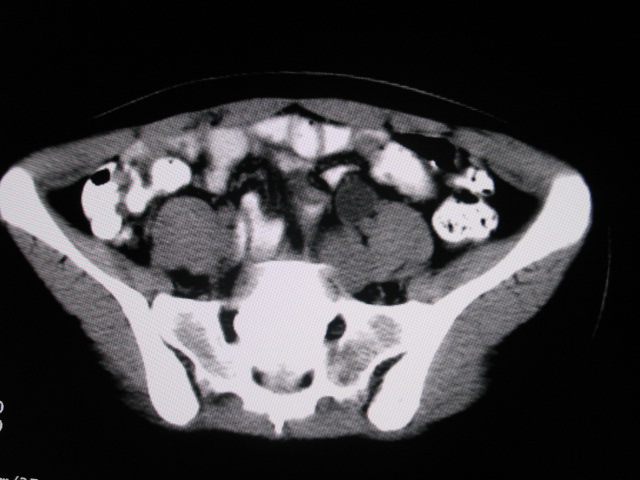

女,28岁,自觉腹部包块一年余

考虑左侧双肾盂双输尿管畸形,其中一输尿管末端梗阻(不排除异位开口可能)并相应之肾盂及输尿管明显扩张积水。

考虑左侧双肾盂双输尿管畸形,其中一输尿管末端梗阻并输尿管肠管样扩张盂曲、肾盂囊状扩张积水。

支持;左侧双肾盂双输尿管畸形,其中一输尿管末端梗阻并输尿管肠管样扩张迂曲、肾盂囊状扩张积水。

左双肾盂输尿管畸形.其一输尿管远端输尿管囊肿引起一肾盂输尿管积水.

考虑左侧双肾盂双输尿管畸形,其中一输尿管末端梗阻(不排除异位开口可能,不知病人有无不自觉溢尿,有可能开口于阴道或宫颈,也可下端为盲端)并相应之肾盂及输尿管明显扩张积水。

术后证实是左侧双肾盂双输尿管畸形,巨输尿管巨肾盂症